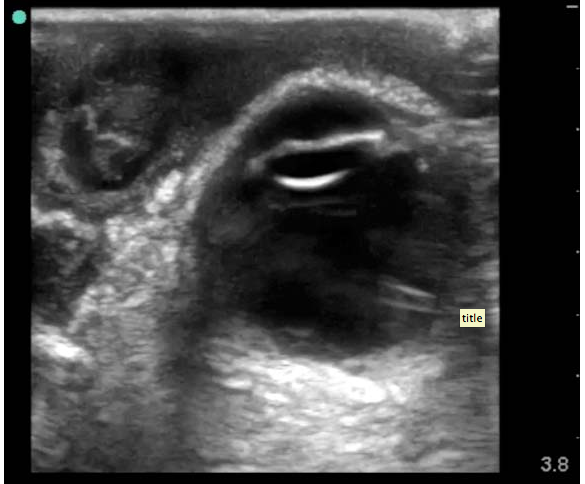

“41-year-old male who presents to the ED with concerns that his left eye is progressively getting more swollen. He’s had some increasing eye pain and purulent drainage over the past six days. At first he thought that he was just having really bad seasonal allergies, but today, he started feeling a “pulling sensation” on the medial aspect of his left eye. He denies any headache, diplopia, sinus pain, rhinorrhea, nausea, vomiting, or recent trauma. He does note a subjective fever at home, and his temperature is 38.2°C in the ED. His vital signs otherwise demonstrate tachycardia to 123 bpm, but a normal blood pressure, oxygen saturation, and respiratory rate. Your intern has asked the nurse to obtain a visual acuity on the patient and he is systematically going through his ocular exam when you walk by the room to check on him. He comes out of the room to give you an update on what he’s discovered so far. The patient has tenderness to palpation over his left medial orbit and possible entrapment on ocular exam. He has no additional pain with extraocular movement and no diplopia, but has so much periorbital edema that it wasn’t possible to get a consistent Tonopen measurement. There doesn’t appear to be any fluorescein uptake on the slit lamp exam, and other than conjunctival injection and the lid swelling, the patient has a normal ocular exam.

It is now about 4:30 pm and you know that in 30 minutes, all consultants turn into pumpkins and their pagers magically stop working. As you are about to ask your intern what he wants to do next, the medical student pulls up the ultrasound machine that the intern asked her to wheel over and hands it to him. He takes the linear array transducer and performs an ocular ultrasound at the bedside. He saves the following images: what do you see?”

Screen shot 2013-01-07 at 1.57.18 PM